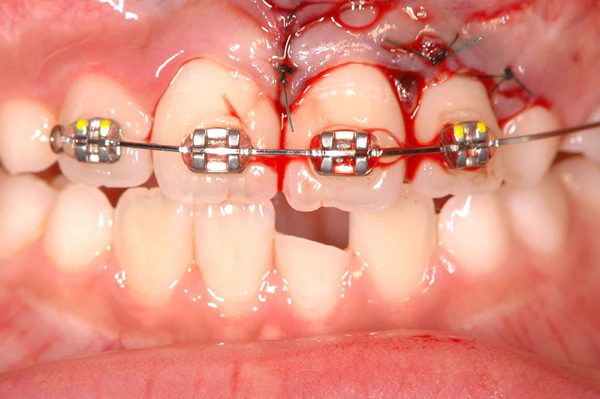

写真は2本の歯の複雑な歯根破折と別の1本の挺出性脱臼(折れずに抜けている)、および、上あご真ん中で大きな歯槽骨骨折を起こした患者さんの治療前の写真です。

多くの損傷があり、処置はそれほど簡単ではないのですが、けがをした直後であったこと、受傷歯が幼若永久歯(歯根がまだ十分に完成していない)であったこと、処置が正確であったことから、抜歯も考えなければならないような歯が、神経も残すことができ、何事もなかったかのように治っています。